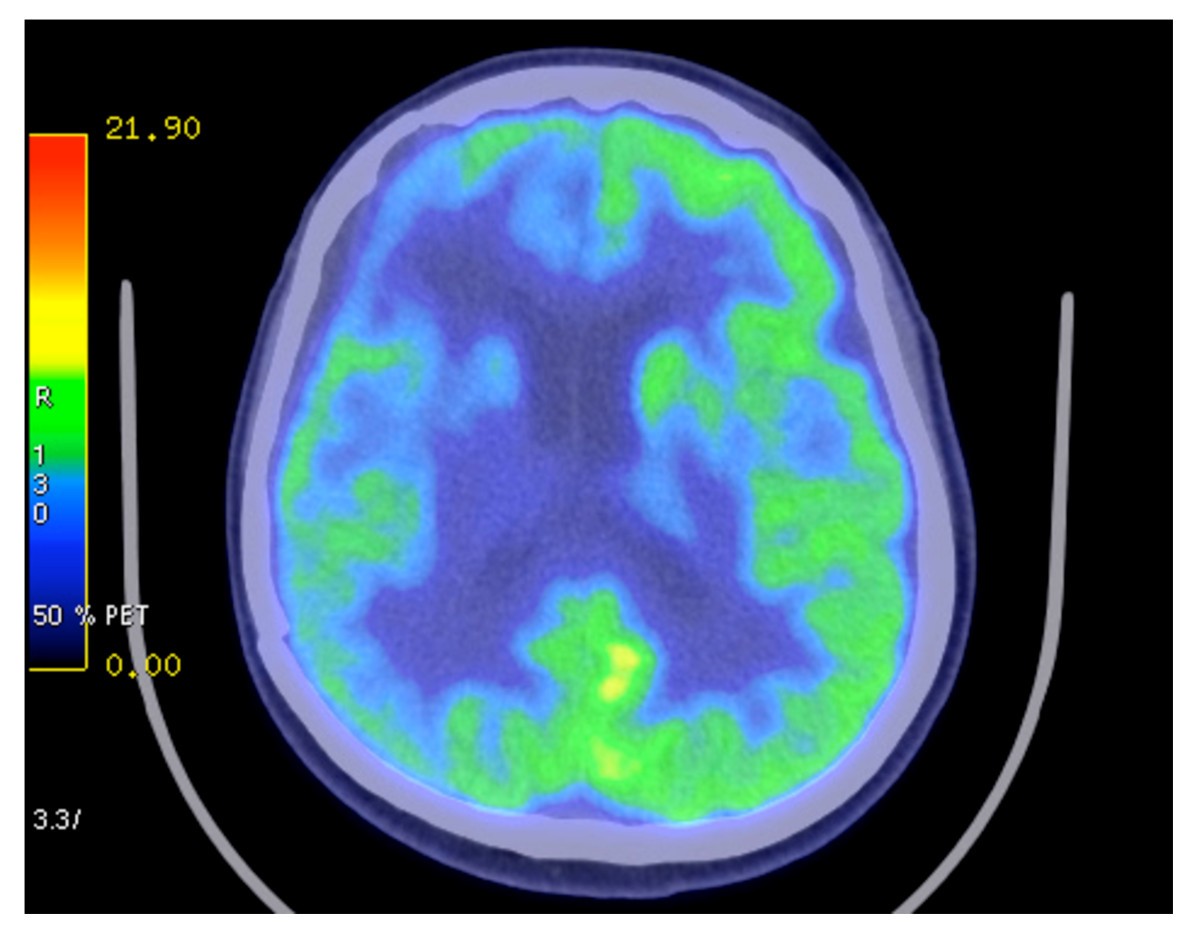

Tumor area (cm 2 ). Tumor area was significantly smaller .... Looked at tumor metabolism and the effect of the ketogenic diet has on it, specifically. Glioblastoma, a form of brain cancer, is an aggressive brain tumor found in adults. Ketogenic diet for patients with recurrent glioblastoma. Pilot study of ketogenic diet in recurrent glioblastoma. Another advantage of a ketogenic diet in the treatment of glioblastoma is the accessibility and affordability of changing nutritional habits for all socioeconomic classes. Prior to his study, woolf et. Ketogenic diet, glioblastoma, pilot study, lessons learned, blood ketones. Limiting dietary carbohydrates inhibits glioma growth in preclinical models. This unique clinical trial, only being offered at uc, will allow experts to follow patients with glioblastoma to see if a ketogenic diet coupled with standard treatment (chemotherapy and radiation). Therefore, the ergo trial (nct00575146) examined feasibility of a ketogenic diet in 20 patients with recurrent glioblastoma. Ketogenic diet, modified ketogenic diet, medium chain triglyceride diet, glioblastoma. We conducted a feasibility study to investigate the use of ketogenic diets (kds) as an adjuvant therapy for patients with glioblastoma (gbm), investigating (i) trial feasibility; Ketogenic diet, dietary supplementary products provided by tavarlin. Schwartz ka, noel m, nikolai m and chang ht (2018) investigating the ketogenic diet as treatment. Glioblastoma (gbm) is an aggressive primary human brain tumour that.

Glioblastoma, a form of brain cancer, is an aggressive brain tumor found in adults. Another advantage of a ketogenic diet in the treatment of glioblastoma is the accessibility and affordability of changing nutritional habits for all socioeconomic classes. Management of glioblastoma multiforme (gbm) has been difficult using standard therapy (radiation the ketogenic diet is used commonly to treat refractory epilepsy in children and, when administered. The ketogenic diet, also called the keto diet, focuses on getting most of your calories from fat and some from protein, while drastically cutting carbohydrates. Ketogenic diet, dietary supplementary products provided by tavarlin. Limiting dietary carbohydrates inhibits glioma growth in preclinical models. Using ketogenic diets to aid in cancer therapy is a controversial topic without robust human trial data.

The ketogenic diet is becoming known for being beneficial in so many areas of health and medicine as we mentioned above, the ketogenic diet is one that's very low in carbohydrates, moderately low in. Schwartz ka, noel m, nikolai m and chang ht (2018) investigating the ketogenic diet as treatment. Limiting dietary carbohydrates inhibits glioma growth in preclinical models. Glioblastoma, a form of brain cancer, is an aggressive brain tumor found in adults. The ketogenic diet was developed at john hopkins hospital in the 1920s as a natural cure for it is still official government dietary policy today, due to the influence of the vegetable oil industry which. Below follows an account by one of our patients about his case. Standard of care increase glioblastoma energy metabolism? The ketogenic diet is becoming known for being beneficial in so many areas of health and medicine as we mentioned above, the ketogenic diet is one that's very low in carbohydrates, moderately low in. The ketogenic diet is the most popular diet trend in our world today. The purpose of the ketogenic diet is to maintain a state of ketosis, wherein the body's primary energy source is this time the ketogenic diet is being promoted as much more than a therapeutic agent. Following a keto diet causes your metabolism to switch from burning sugar to burning fat and ketones as a primary body fuel. We spoke to maria petzel. Glioblastoma (gbm) metabolism has traditionally been characterized by a dependence on aerobic glycolysis, prompting use of the ketogenic diet as a potential therapy. Therefore, the ergo trial (nct00575146) examined feasibility of a ketogenic diet in 20 patients with recurrent glioblastoma. Glioblastoma multiforme accounts for 12% to 15% of all intracranial neoplasms and affects 2 to 3 for this reason a restrictive calorie ketogenic diet, similar to that used in children to control drug. Another advantage of a ketogenic diet in the treatment of glioblastoma is the accessibility and affordability of changing nutritional habits for all socioeconomic classes. Limiting dietary carbohydrates inhibits glioma growth in preclinical models. Using ketogenic diets to aid in cancer therapy is a controversial topic without robust human trial data. Ketogenic diet for patients with recurrent glioblastoma. Management of glioblastoma multiforme (gbm) has been difficult using standard therapy (radiation the ketogenic diet is used commonly to treat refractory epilepsy in children and, when administered. Following a ketogenic diet plan is useful for improving insulin tolerance and reducing inflammation. We conducted a feasibility study to investigate the use of ketogenic diets (kds) as an adjuvant therapy for patients with glioblastoma (gbm), investigating (i) trial feasibility; Glioblastoma (gbm) is an aggressive primary human brain tumour that. Ketogenic diet, dietary supplementary products provided by tavarlin. Prior to his study, woolf et. Management of glioblastoma multiforme using standard therapy together with a restricted ketogenic diet: The ketogenic diet, also called the keto diet, focuses on getting most of your calories from fat and some from protein, while drastically cutting carbohydrates. A rationale for ketogenic diet as experimental glioma therapy. Pilot study of ketogenic diet in recurrent glioblastoma. This unique clinical trial, only being offered at uc, will allow experts to follow patients with glioblastoma to see if a ketogenic diet coupled with standard treatment (chemotherapy and radiation). Looked at tumor metabolism and the effect of the ketogenic diet has on it, specifically.